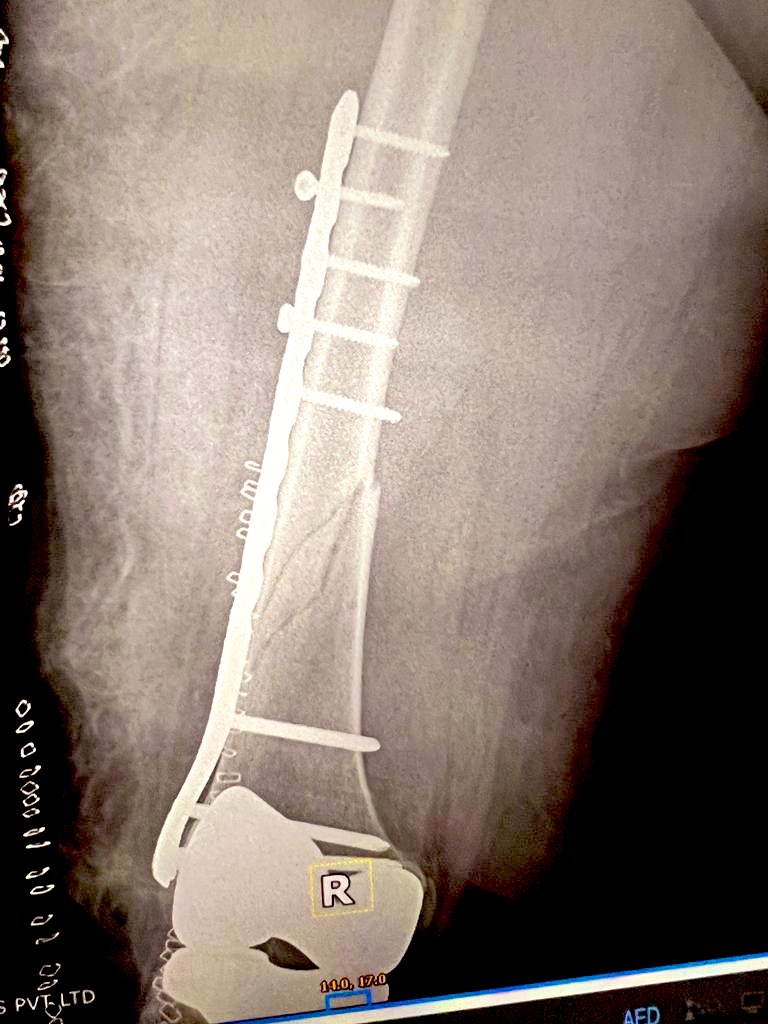

They finally decided to use β€œless invasive variable locking plate” from Synthes for her.

The end result was marvellous, with small 3 inch incision & few punctures to pass screws on proximal end of implant

Exactly 80 days after her fracture & fixation we took another X Ray.

It showed good recovery, increasing bone density & some micro trabecular patterns.

We allowed full weight bearing & reiterated again to go slow no hurry.